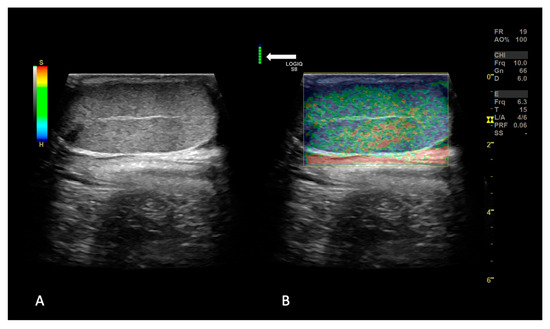

Imaging techniques play a fundamental role in daily practice to achieve a final diagnosis in companion animals and proper treatment plans.

All the available imaging techniques provide specific information, and it is important to choose the proper technique to confirm or exclude the suspected diagnosis.

This Special Issue of Animals aims to collect new advances in Veterinary Imaging Techniques and Radiation Therapy, facilitating a deeper understanding of specific imaging techniques and more effective treatments for companion animals.